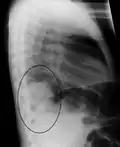

Right upper lobe pneumonia as marked by the circle. -